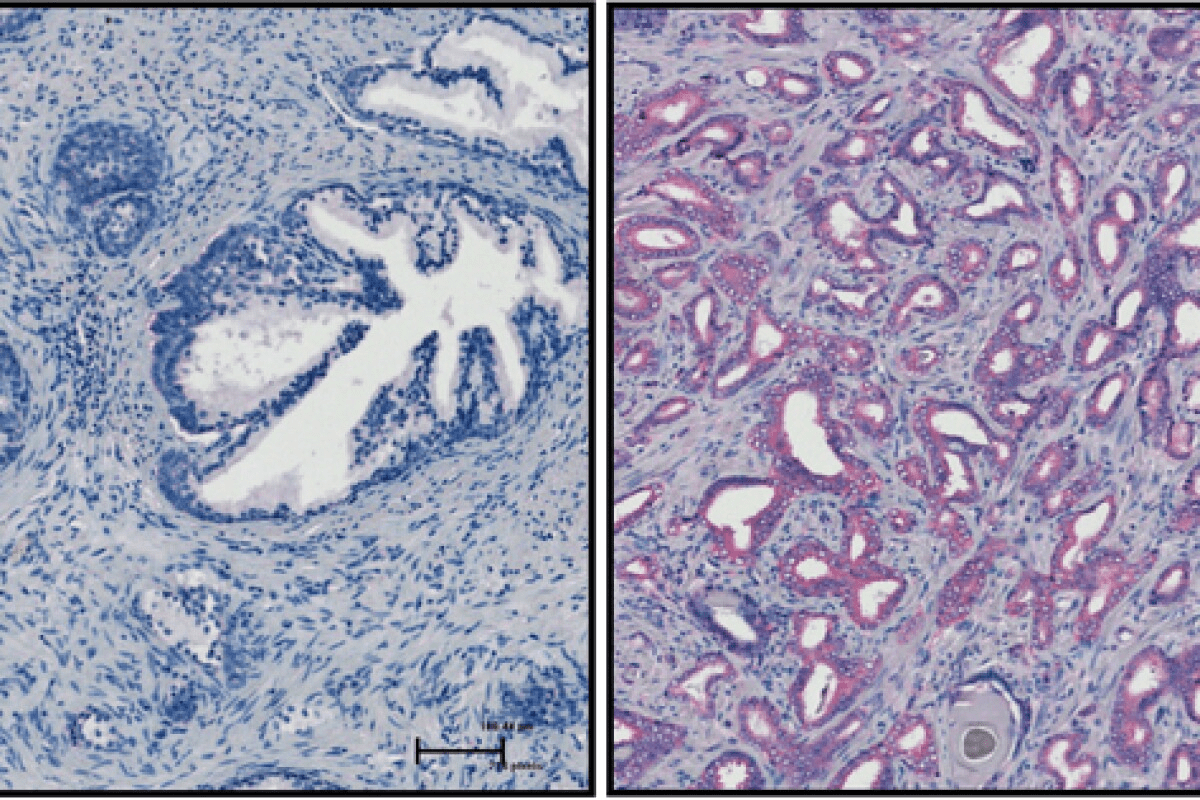

image 1761505079941 LIV Hospital

image 1761505084542 LIV Hospital